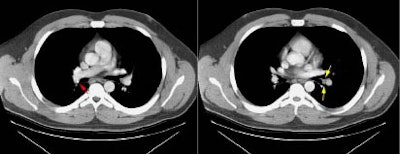

Example of the normal hilar interstitium: The images below are from a patient without bronchogenic carcinoma. The images demonstrate normal hilar lymphatic tissue (yellow arrow right image) which appears as a low density region between the bronchus and pulmonary vessel. A small calcified node is seen on the right (red arrow) in this patient with prior granulomatous disease. NOTE: Click image to enlarge.